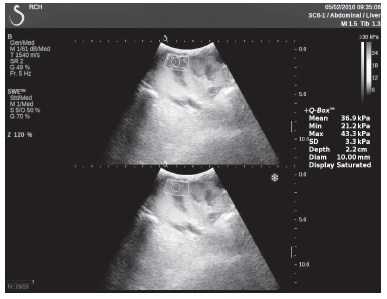

Клинический пример из первой группы. Пациент М., с хронической почечной недостаточностью. Трансплантация почки произведена от живого родственного донора. Трансплантат находится в правой подвздошной области. При нормальном функциональном состоянии трансплантата, показатели цветовой и спектральной допплерографии оценивались как удовлетворительные, с индексом резистентности не более 0,60 (рис. 1); показатели жесткости паренхимы почечного трансплантата при УЭСВ на различных участках составили от 20,05 до 29,18 кПа (рис. 2-4).

Рисунок 2. Исследование в режиме ультразвуковой эластографии сдвиговой волны у пациента М.: жесткость паренхимы в зоне медиального края трансплантата 19,8 кПа